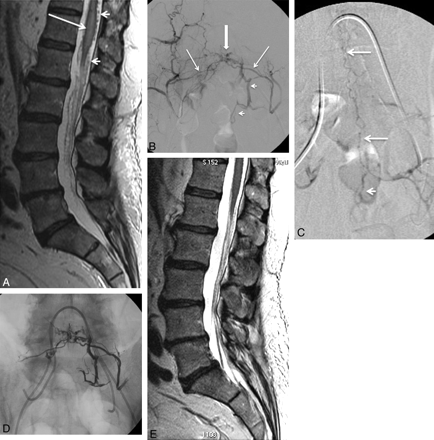

A, Sagittal T2-weighted MR image in a 67-year-old patient with progressive bilateral leg weakness, gait instability, and tingling in both hands shows increased signal intensity in the spinal cord (arrows) and perimedullary flow voids, consistent with venous hypertension. B, Cerebral angiogram shows a dural AVF with venous drainage into the petrous, anterior medullary, and spinal perimedullary veins (arrows). C and D, The fistula is supplied by the meningo-hypophyseal trunk of the right internal carotid artery (arrow, C) and the petrous branch of the right MMA (arrow, D). E, A microcatheter is positioned in the MMA, just proximally to the fistula (arrow), and embolization is then performed with Onyx. F, The postembolization angiogram shows obliteration of the fistula.